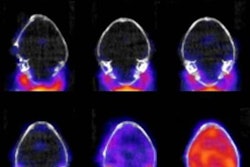

(a) Axial, (b) sagittal, and (c) coronal fetal T2-weighted MR images were obtained in a 29-year-old woman with confirmed Zika virus infection, initially seen for characteristic rash at 12 weeks of gestational age. (d) Axial postnatal CT image and (e-g) axial and (h) coronal T2-weighted MR images were obtained in her neonate. The fetal MR images obtained at 34 weeks (a-c) show asymmetrical ventriculomegaly with a septation in the right occipital horn (arrowhead on a), small frontal lobes, thinning of the occipital parenchyma (left worse than right), underdeveloped sylvian fissures, and regions of thickened cortex, as in the right frontal lobe, which is suggestive of polymicrogyria (arrow on a). There is abnormal, increased signal intensity in the white matter. The postnatal CT image (d) obtained in the 22-day-old neonate shows punctate calcifications at the gray matter-white matter junction and asymmetrical ventriculomegaly. The T2-weighted MR images obtained at 26 days (e-h) show septation in the ventricle (arrowhead on e). Note how the right ventricle has relatively decreased in size compared with the prenatal image, whereas the left ventricle has increased in size. Underrotation of the hippocampus (arrowheads on f) is demonstrated. There is clear asymmetry of the gyral pattern on g, which is relatively smooth in the left occipital region, with abnormal folds in the right occipital and frontoparietal regions (arrows on g). Subependymal cysts are visualized on h, which are not seen on fetal MR images."The severity of the cortical malformation and associated tissue changes and the localization of the calcifications at the gray-white matter junction were the most surprising findings in our research," said Dr. Fernanda Tovar-Moll, PhD, in a statement released by RSNA.